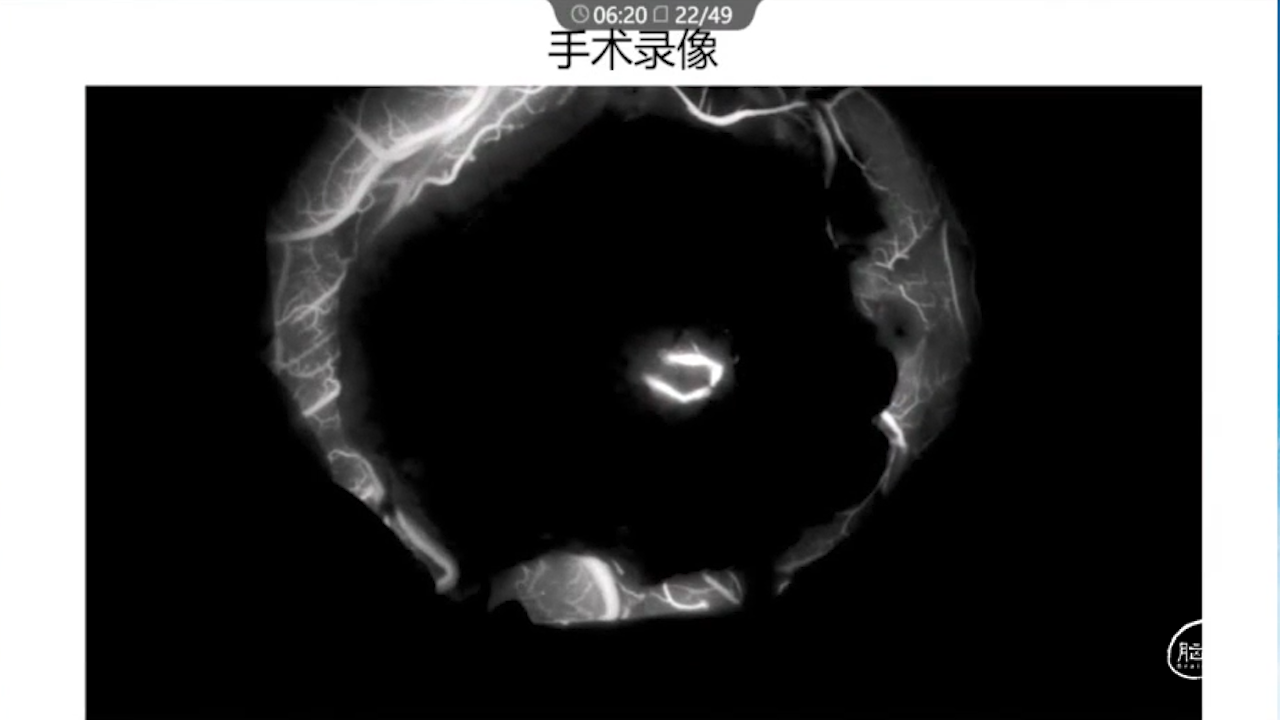

7、术中辅助技术:实时定位并保护静脉,监测其通畅性(荧光造影、Flow800)。